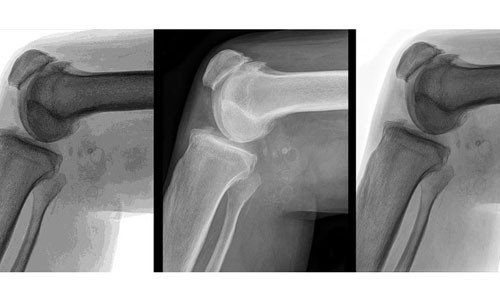

Viêm xương khớp gây đau khớp, cứng khớp; tình trạng sưng và đau có thể nặng lên theo thời gian, thường gặp ở đầu gối, hông và bàn tay. Nguyên nhân là do sụn khớp bị vỡ, khiến khả năng bạo vệ các đầu xương bị ảnh hưởng. Thừa cân có thể làm tình trạng viêm khớp tồi tệ hơn do tăng gánh nặng cho khớp xương.

Béo phì có thể làm cho viêm khớp thêm trầm trọng bởi trọng lượng cơ thể càng nặng, các khớp ở hông, đầu gối càng phải chịu nhiều áp lực. Còn nếu đã bị viêm khớp thì sự “đè nén” của trọng lượng cơ thể càng khiến khớp nhanh hư hại.

Theo Quỹ Viêm khớp, mỗi trọng lượng thừa sẽ khiến khớp gối tăng thêm áp lực tương đương 1,8kg. Vì vậy, 1 người thừa 4,5kg sẽ khiến gối chịu thêm 18kg áp lực. Nếu 1 người thừa 44kg kg cân nặng, thì đầu gối sẽ chịu thêm 181kg áp lực.